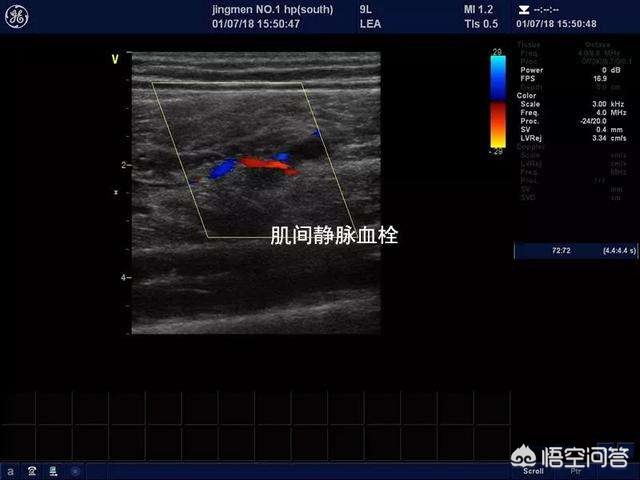

如果您发生这种情况的时候正处于住院期间,那么建议您一定与您的主治医生沟通,做一个下肢的血管彩超检查,明确是否存在下肢静脉血管的血栓形成或者是微小血栓形成。彩色超声检查对于诊断下肢静脉血栓形成特异性比较高,准确率也比较高,而且费用也不是特别贵,一般在100元左右。